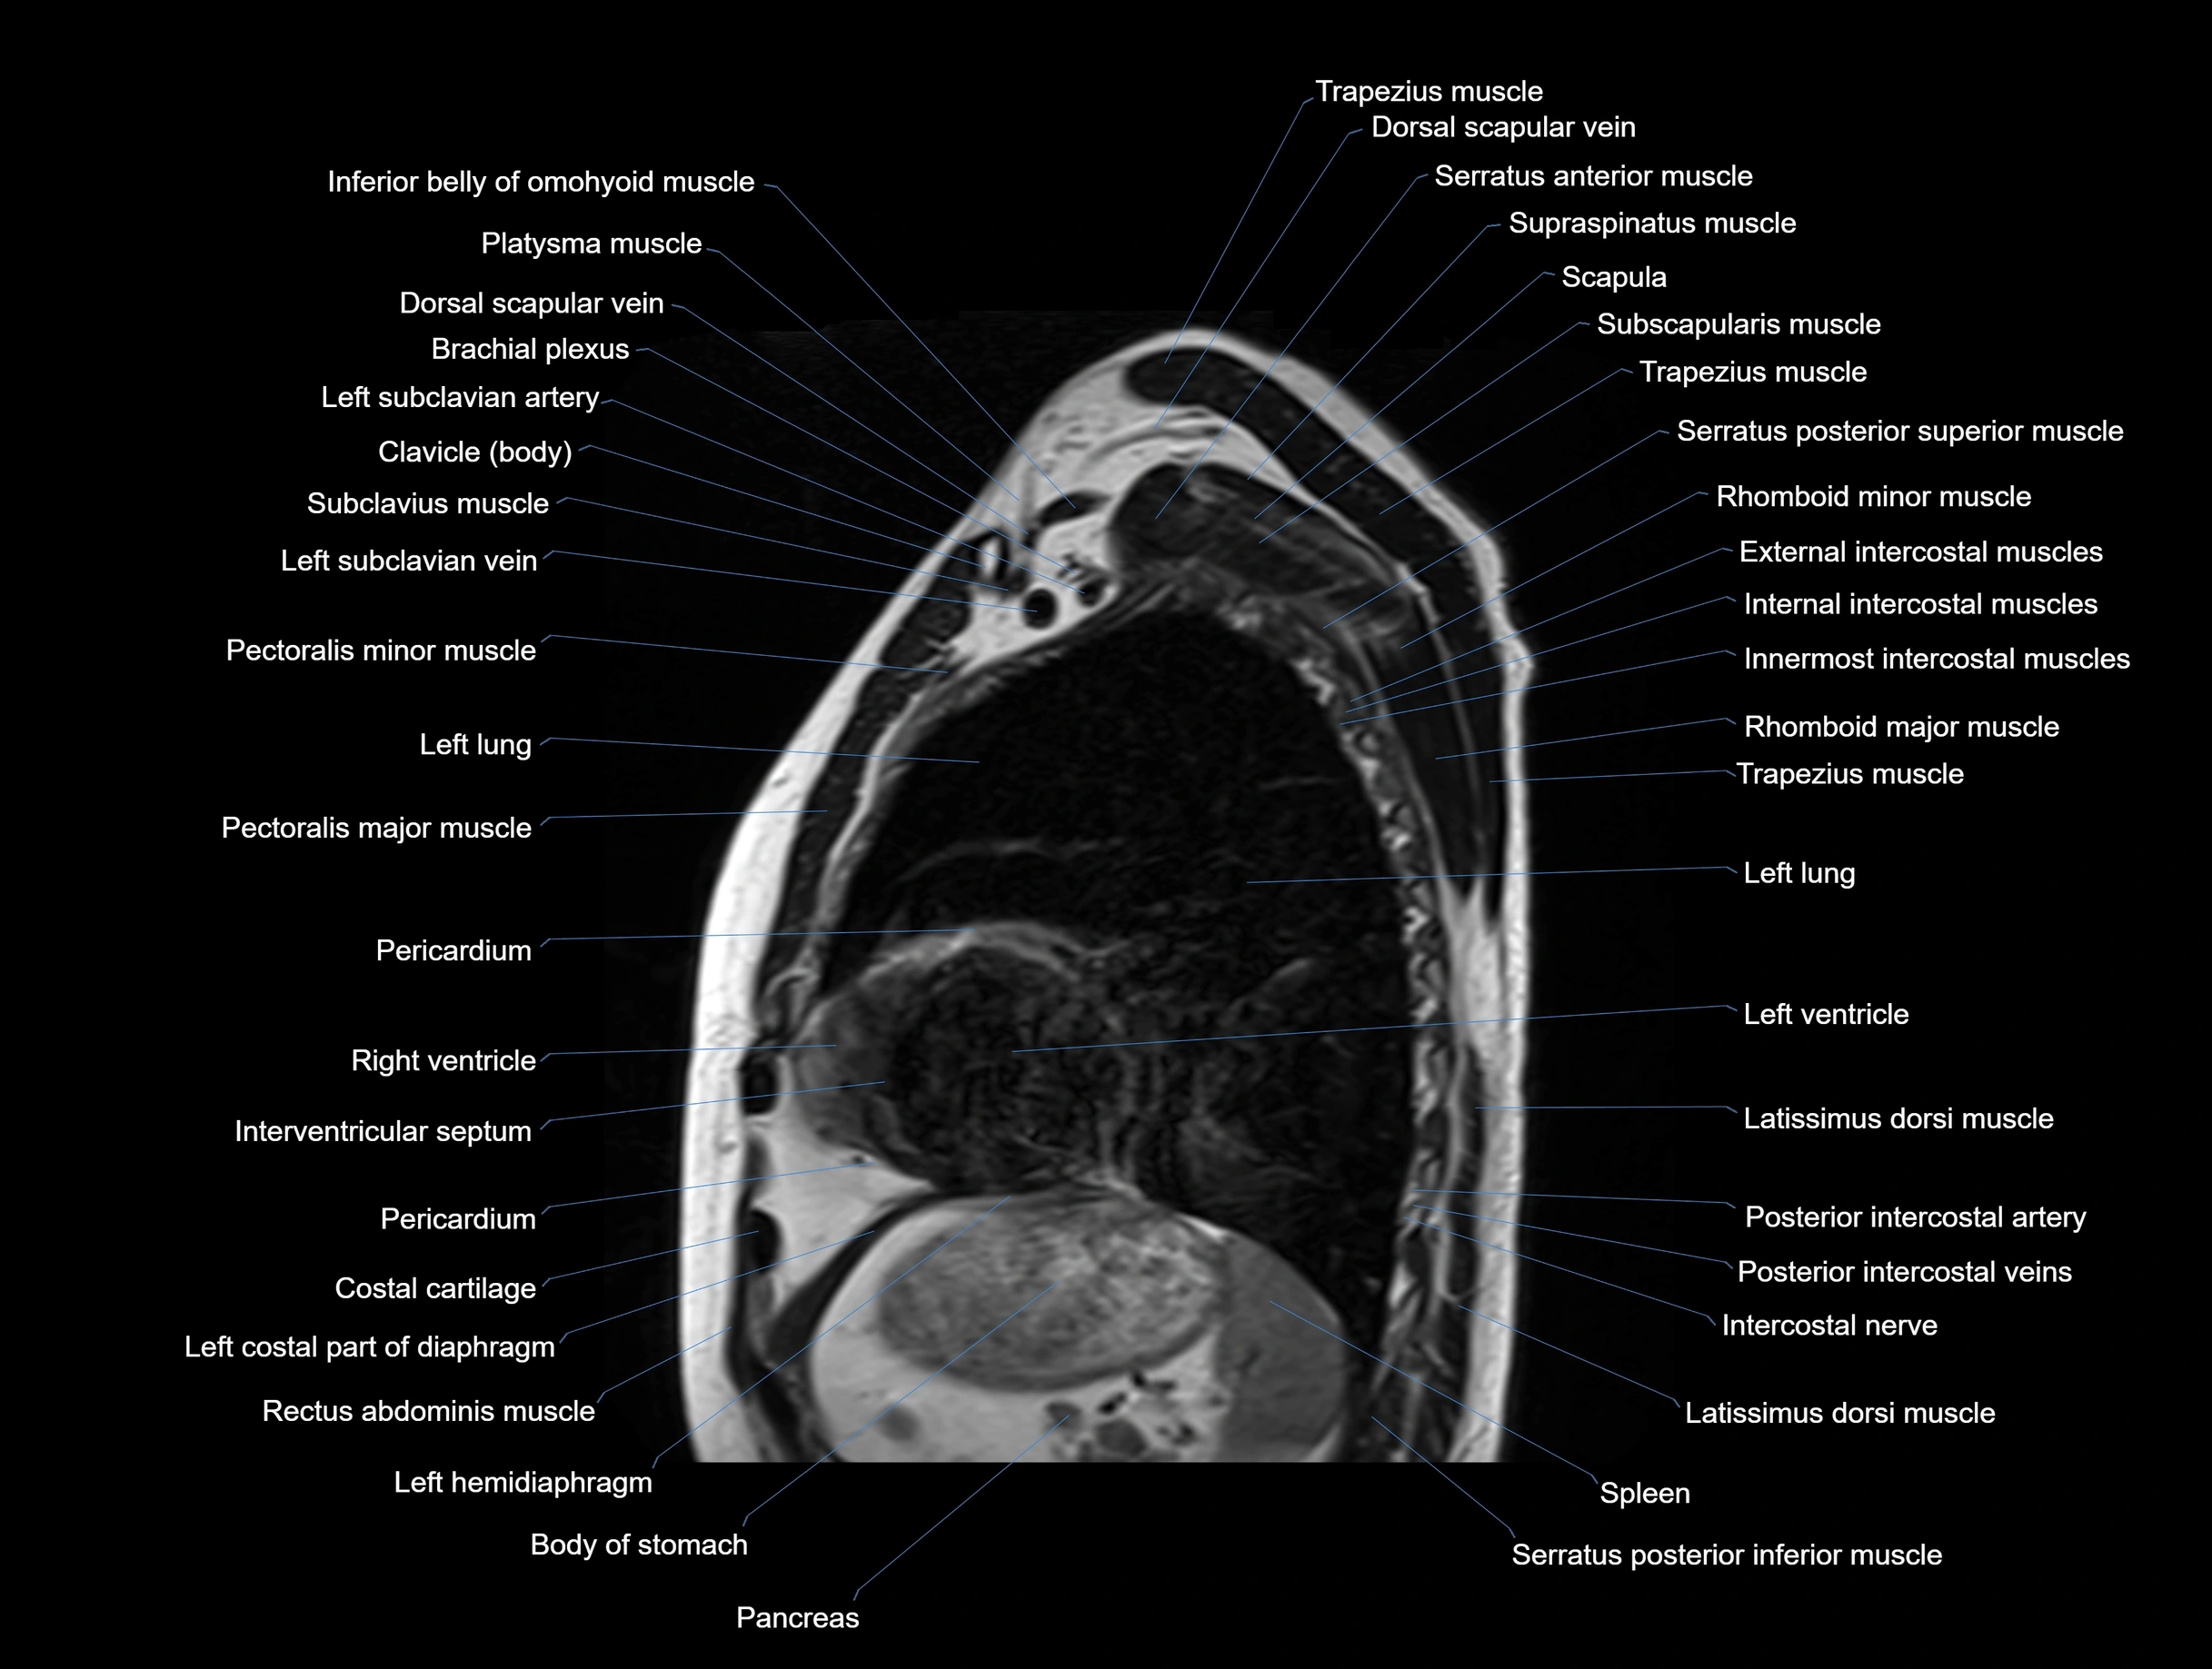

MRI images